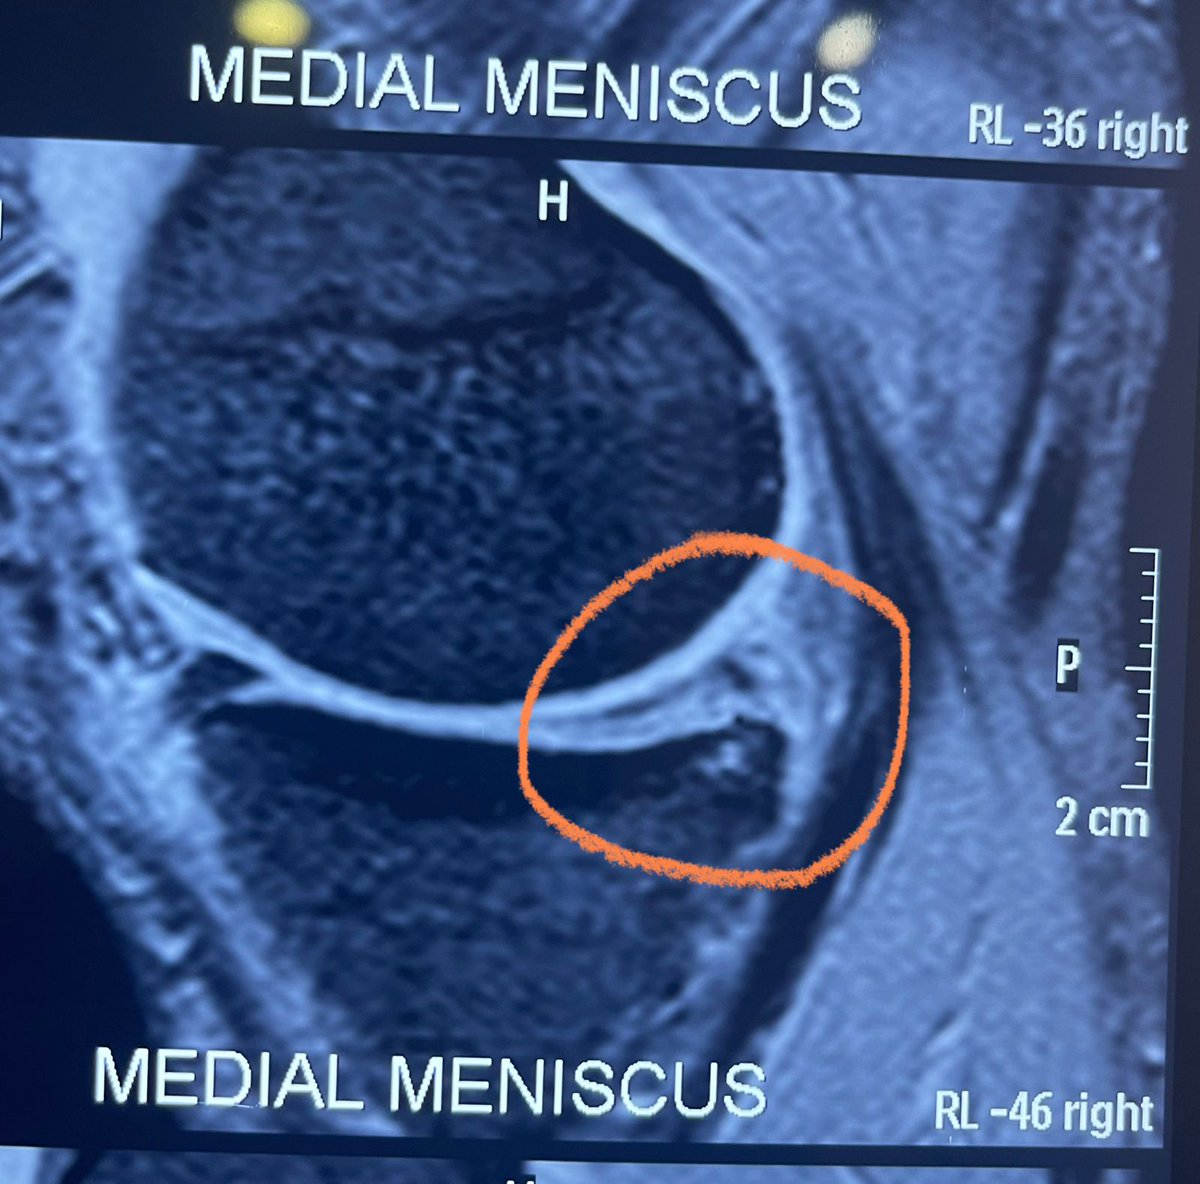

Konda Vishweshwar Reddy

Konda Vishweshwar Reddy@KVishReddy·

Had a knee meniscus tear 6 months ago. Neglected it, the tear got bigger. Had a Minimal invasive knee surgery last night. In the hospital till Monday. Could not postpone it further. Will be back in action in two weeks.

Konda Vishweshwar Reddy tweet mediaKonda Vishweshwar Reddy tweet mediaKonda Vishweshwar Reddy tweet media